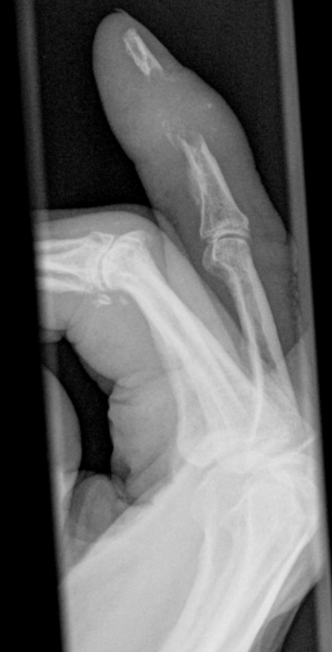

Metastatic bone destruction distal phalanx